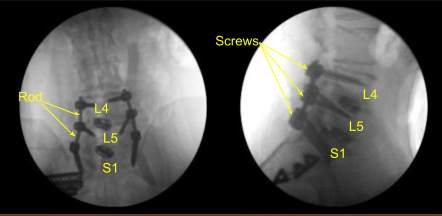

The patient was draped sterilely. CT scan was obtained, and data was transferred to the neuronavigation computer. Neuronavigation techniques were used to reposition and replace bilateral sacral screws which were upsized both in diameter and length until tight.

We also replaced the left L4 and L5 pedicle screws similarly with a new track screw aided by decorticating with electric high-speed drill, cannulating with navigated pedicle finder, palpating for breaches, measuring the depth, under tapping by 1 mm and placing the pedicle screws without difficulty.

Additional CT scans were performed showing correct positioning of all the pedicle screw hardware. Neuromonitoring signals were stable. Next, we decorticated bilateral transverse processes and facet joints including sacral ala from L4 to S1 bilaterally with electric high-speed drill for the arthrodesis. The wound was irrigated copiously.

Precut-precontoured titanium rods were selected, contoured further and placed across the tulips from L4 to S1 bilaterally and secured with locking caps which were all final tightened with a torque and anti torque device. AP and lateral fluoroscopy was used to confirm appropriate sizing and positioning of the rods.